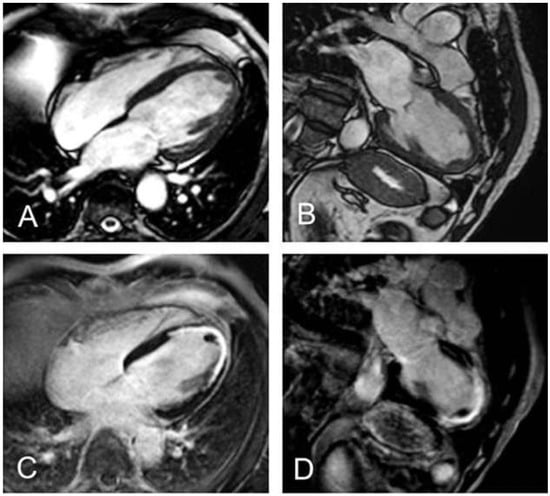

Figure 4. Figure 4. Darstellung eines Thrombus im LV-Apex. Sichtbar sowohl in den Cineaufnahmen im 4- und 2-Kammer-Blick (A,B) als auch in den Late-gadolinium-enhancement-Aufnahmen im 4- und 2-Kammer-Blick (C,D).

Kardiale Thromben

Eine Komplikation, die wesentlich zu Mortalität und Morbidität herzinsuffizienter Patienten beiträgt, ist das Auftreten eines Ventrikelthrombus (Figure 4). Sowohl bei Patienten mit ischämischer Kardiomyopathie als auch bei Patienten nach akutem Myokardinfarkt können linksventrikuläre Thromben auftreten. Das Herz-MRI zeigt die höchste Sensitivität und Spezifität zur Detektion von Ventrikelthromben verglichen mit der transösophagealen bzw. transthorakalen Echokardiographie und auch der kontrastmittelverstärkten Echokardiographie [58,59].